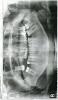

Zeva Опубликовано 22 января, 2013 Поделиться Опубликовано 22 января, 2013 (изменено) Добрый час господа .По прошествии 10 лет решил начать лечить свои зубы . 33 года .Противопоказаний нет.Уважаемые доктора . Мне бы хотелось понять оптимальный план лечения (протезирования) в данной ситуации (снимок)Был на приеме у специалиста . С ее слов практически весь верх надо уничтожать и ставить мост . С нижней частью тоже непонятно . Ограничение по финасам присутствует. Хотелось бы придумать такую схему лечения, с использованием имплантантов и обычного протезирование, с перспективой лечения на ближайший год и последующей заменой на имплантанты , с сохранением своих зубов, если это имеет смысл.Прошу вас высказать свое мнение . Завтра пойду еще в одну клинику на консультацию.С уважением Всеволод. Изменено 22 января, 2013 пользователем Zeva Ссылка на комментарий

IvanK Опубликовано 22 января, 2013 Поделиться Опубликовано 22 января, 2013 1. Консультация ортодонта.2. Ортопед3. Терапевт: 17,12,25, 26, 37, 42, 45, 47...4. Удаление: 14, 28, 385. Imp 14,16,36,46 1 Ссылка на комментарий

Mane Опубликовано 22 января, 2013 Поделиться Опубликовано 22 января, 2013 полностью поддерживаю пост вышедобавлю еще - синус-лифтинг справа Ссылка на комментарий